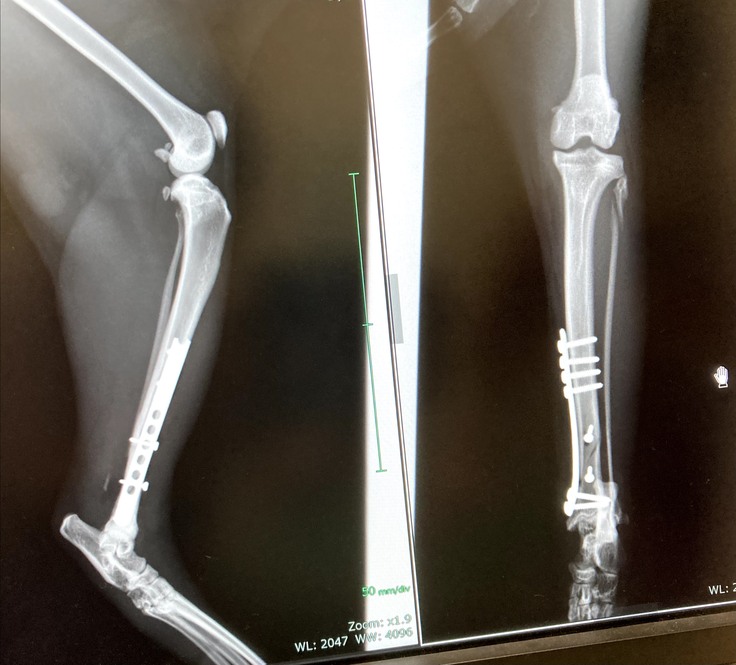

今回このくーちゃんが左後ろ足を開放性剝離骨折してしまいました。骨が3分割と小さな骨に分かれてしまっていてプレートを入れ小さい骨はピンで止めていただき手術は大成功しました。しかし創部に感染があった為術後も入院が長引きました。退院して2日後又発熱しぐったりし受診、感染からの熱か再入院。その退院の2日後にまた患部が凄く熱くぐったりし受診。今回は手術の部位が再度骨折してしまっていました。毎日ケージの中でほぼほぼ寝たきりであったのですが何故か再度骨折。かなり痛みもある様で可哀想に熱もでていました。私は死んでしまうのではと夜中に何度も見に行く日々が続きました。

先生のおかげで綺麗に修復していただきました。くーちゃんよく頑張ったね

上が7月10日、下が15日 真ん中の小さい骨がずれてピンが横を向いてしまっています。

9月17日上の写真です。空いていた穴が少しずつ塞がって来ているとの事です。